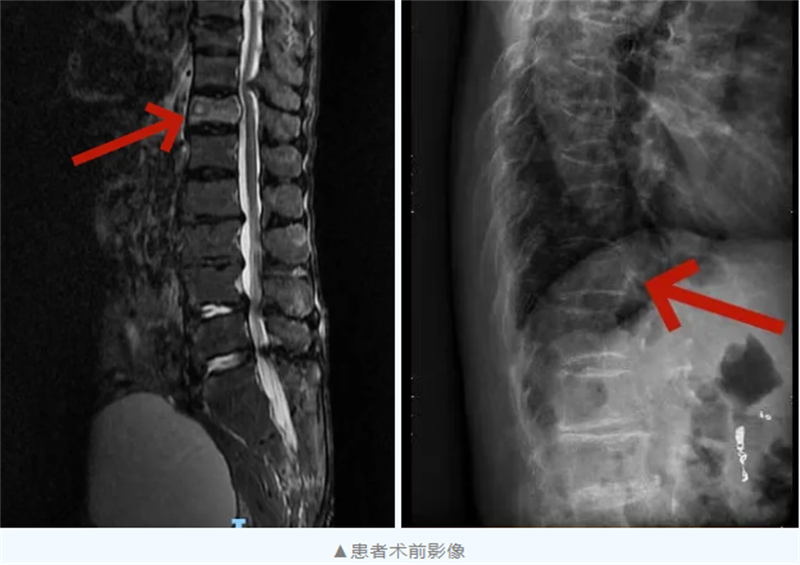

黃奶奶因腰背嚴重疼痛無法站立,來院檢查后,診斷為胸11椎體壓縮性骨折。103歲高齡的她,還合并有腎功能不全、高血壓、胸椎管狹窄等多種基礎疾病。傳統開放手術風險極高,長期臥床可能引發壓瘡、肺炎、血栓、心腦血管疾病等并發癥。面對百歲高齡與基礎疾病的雙重考驗,柳州市人民醫院脊柱外科團隊經多學科評估,決定采用“胸11椎體成形術”。

脊柱外科主任胡朝暉主任醫師介紹,胸椎椎體成形術是一種通過穿刺向骨折椎體注入骨水泥的微創技術,具有創傷小、恢復快、安全性高的特點,尤其適合60歲以上骨質疏松性椎體壓縮骨折患者。該手術在局部麻醉下完成,手術切口約2毫米,骨水泥加固椎體后可快速穩定椎體,迅速緩解疼痛。實現當日手術、次日出院,避免長期臥床風險。